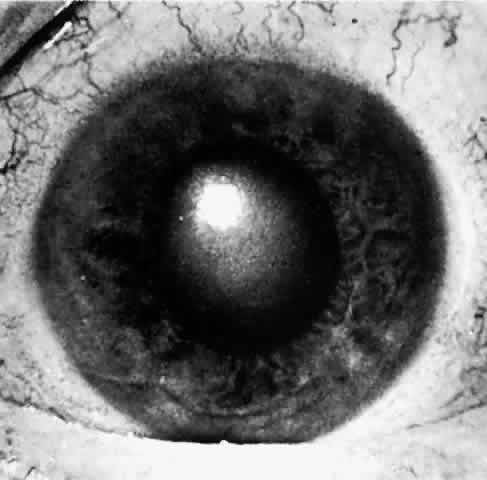

When a patient is seen after an attack that has been in progress for several hours or even days, the eye usually will display decreased vision. The pupil is irregular in shape, nonreactive to light, and resistant to the effects of miotics or mydriatics. It is a common misconception that the intraocular pressure remains elevated in angle-closure glaucoma. In some cases, low tension may be found after aqueous production has decreased while the angle remains closed. If the eye has recovered spontaneously from an attack, the intraocular pressure may be very low due to reduced aqueous formation with or without an open angle. It is important to realize that low pressure following elevated pressure due to acute angle-closure glaucoma does not necessarily mean that the angle-closure attack is over. The pressure will rise as soon as aqueous production resumes, which may be a few hours to many weeks later. The cornea may show Descemet's folds and later recover its transparency but occasionally the corneal edema may persist for weeks after reduction of intraocular pressure. A prolonged iris stromal edema encourages the formation of posterior synechiae in the pupillary area and peripheral anterior synechiae at the level of the angle structures. The destruction of iris tissue results in grayish patches of atrophic iris stroma that may extend to the periphery (Figs. 9 through 11). Tiny white-gray spots with discrete edges may be seen in the pupillary zone. These anterior subcapsular lenticular opacities, best known as glaukomflecken, appear to be the result of damage to the anterior lens epithelium from very high intraocular pressure (Fig. 12).35 Glaukomflecken may result from very high intraocular pressure of any etiology, but are especially characteristic of previous attacks of angle-closure glaucoma.

Fig. 9. Iris atrophy, presumably due to iris ischemia, commonly occurs in sever and prolonged acute angle-closure glaucoma. In this eye, gray, thin, depigmented areas of atrophy of the iris, most marked at the arrows, are present around the pupillary margin clockwise from 8 o'clock to 3:30. Iris atrophy from high intraocular pressure in angle-closure glaucoma usually involves irregular radial sectors of the iris and is most marked near the pupil. In these sectors, the pupil is usually permanently fixed and dilated as a result of the atrophic process.

Fig. 10. In this eye, iris atrophy due to neglected angle-closure glaucoma is so extensive that the pupil is fixed in wide dilation. Some pigment granules from the atrophic iris lie scattered about on the iris stroma. There is a posterior synechia at 2 o'clock at the iris margin. Glaukomflecken are very numerous in this eye but are not visible in this photo because oblique slit illumination is not used; they are visible in Figure 12, in which proper illumination is used. (Photographed by Dr. David Donaldson)

Fig. 12. Same eye as shown in Figures 10 and 11. With oblique slit-lamp illumination, glaukomflecken of Vogt appear as pleomorphic gray-white patches just beneath the anterior lens capsule. These are presumed to be areas of necrotic lens tissue caused by very high pressure. With time, they lie deeper and deeper beneath the anterior lens capsule as new lens fibers are laid down, but they will persist permanently as silent records of previous high intraocular pressure. (Photographed by Dr. David Donaldson)